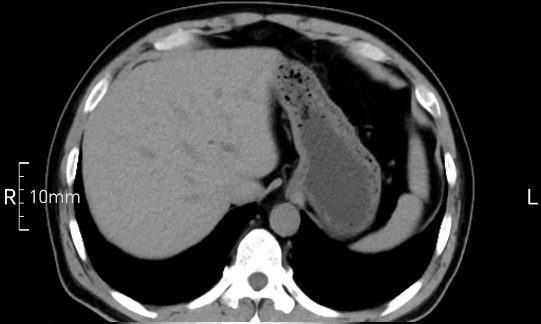

看看下面三幅便知遵醫(yī)囑的重要性。

沒(méi)禁食,胃內(nèi)全是食物,導(dǎo)致胃壁顯示不清。

禁食但檢查前沒(méi)有喝飽,胃未能漲開(kāi),胃壁觀察效果不佳。

完美禁食且喝飽飽,胃壁完美展現(xiàn)。